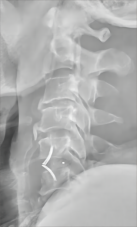

2.颈椎后路减压固定技术

颈椎后路减压技术适用于:脊髓型颈椎病伴发育性或多节段退变性椎管狭窄者;多节段OPLL;颈椎黄韧带肥厚或骨化所致脊髓腹背受压者。有节段性不稳定者可以同时行侧块钛板螺钉或经椎弓根螺钉内固定、植骨融合术。我科在区域内率先开展颈椎单开门、双开门技术,颈椎椎板切除减压椎弓根内固定术,均获得满意疗效。